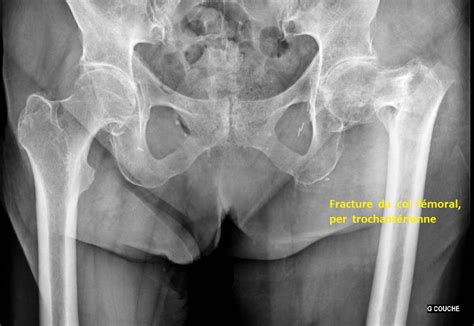

Fracture Col Du Femur - Fichier:Fracture du col du fémur.jpg — Wikipédia : Les fractures du col du fémur ou du trochanter touchent essentiellement les personnes âgées et surtout les femmes atteintes d'ostéoporose.. Le fémur est l os de la cuisse. Cela cache peut etre une fragilite osseuse ou autre chose il convient de profiter de cette fracture pour faire faire tous ça dépend du traitement. Ces cookies permettent d'obtenir des statistiques de fréquentation anonymes ainsi que des rapports d'erreur lors de la visite du site, afin d'optimiser son ergonomie, sa navigation et ses contenus. Les fractures du fémur les plus courantes sont celles au niveau du col du fémur, notamment chez les personnes âgées souffrant d'ostéoporose. Les ateliers de prévention des chutes.

Les fractures du col du fémur représentent avec les fractures de la région trochantérienne le groupe de fractures de l'extrémité supérieure il s'agit des fractures qui atteignent le col du fémur, le plus souvent, à la suite d'une chute.

Les patients chez qui a été installée une prothèse totale de la hanche ont montré un risque de mortalité diminué de 20%. Fracture du col du fémur. Les fractures du col du fémur ou du trochanter touchent essentiellement les personnes âgées et surtout les femmes atteintes d'ostéoporose. La fracture de l'extrémité supérieure du fémur (fesf) est la complication la plus grave de l'ostéoporose, du fait des risques de complications entraînant des conséquences en termes d'incapacité physique permanente, de morbidité et pouvant être la cause du décès. Les personnes âgées qui se sont fracturées le col du fémur ont parfois du mal à récupérer. La fracture du col du fémur, aussi appelée « fracture de la hanche », est une fissure qui intervient près de l'articulation de la hanche après un choc. Il ne faut pas prendre la fracture du col du fémur à la légère, en effet 20% des personnes qui en ont subit une décèdent dans l'année et la moitié garderont des séquelles à vie. Le fémur est l os de la cuisse. Pour les 55.000 fractures du col du fémur annuelles en france, un seul traitement: Une fracture de l'extrémité supérieure du fémur (ou fracture de l'extrémité proximale du fémur), appelée couramment « fracture de la hanche » ou fracture du col du fémur. La tête du fémur est déjà plus fragile que le reste du squelette en temps normal et devient plus vulnérable encore. Un an après leur admission à l'hôpital, 23 % des patients sont. On compte plus de 60 000 cas par an en france, ce nombre augmentant chaque année, parallèlement au vieillissement de la population.

Une fracture du col a 35a!! Les fractures du col du fémur ou du trochanter touchent essentiellement les personnes âgées et surtout les femmes atteintes d'ostéoporose. Flashcards in fracture col du fémur deck (21). La fracture du col du fémur, aussi appelée « fracture de la hanche », est une fissure qui intervient près de l'articulation de la hanche après un choc. On parle de fracture lorsque cet os est brisé, suite à un traumatisme. La fracture du col du fémur fait partie des fractures de l'extrémité supérieure du fémur. Intervenir le plus tôt possible. Col du fémur — fémur pour les articles homonymes, voir femur. Un an après leur admission à l'hôpital, 23 % des patients sont. Prévention des complications de décubitus. Contrairement à d'autres lésions osseuses, le traitement orthopédique n'est quasiment jamais envisagé pour la fracture du col du fémur. Une fracture de l'extrémité supérieure du fémur (ou fracture de l'extrémité proximale du fémur), appelée couramment « fracture de la hanche » ou fracture du col du fémur. La prévention des fractures du col du fémur repose sur la prise en compte d'un ensemble de facteurs incluant l'ostéodensitométrie et des éléments tels que les antécédents de fractures dans la famille, l'âge, l'état de santé général, etc.